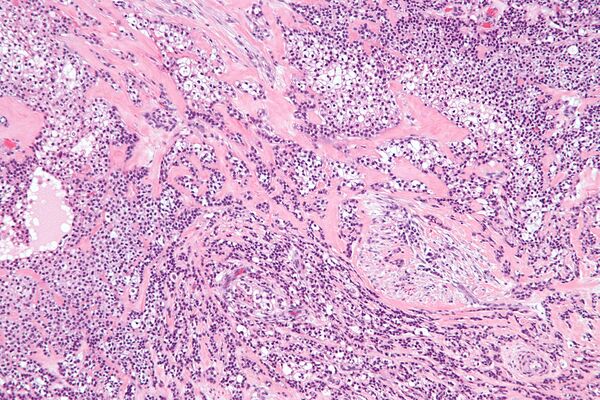

Опухолевые клетки часто располагаются в гнёздах, шнурах (длинных тяжах) и трабекулах (балкообразных структурах), также присутствуют небольшие протоки и кисты. Плоскоклеточные клетки (плоские клетки) и мукоциты (клетки, вырабатывающие слизь) обычно видны как часть структуры опухоли[7].

Одной из уникальных особенностей гиалинизирующей светлоклеточной карциномы является то, что она часто инфильтрирует или распространяется в близлежащие ткани, включая мышцы. В случаях, когда опухоль начинается во рту, она может соединяться с поверхностной выстилкой (эпителием) и распространяться по педжетоидному образцу, то есть опухолевые клетки распространяются по поверхностному слою. Окружающая ткань (называемая стромой) представляет собой смесь плотных, гиалинизированных областей и более рыхлых, фиброзных областей. Такое сочетание типов тканей является характерной чертой этого типа рака[8].